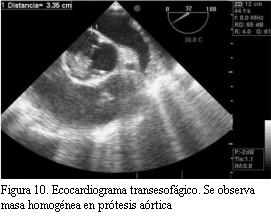

En cara ventricular de la prótesis se visualiza masa homogénea de aproximadamente 1,8 cm que protruye al tracto de salida del ventrículo izquierdo.

ETE (figuras 10 y 11): prótesis mecánica monodisco aórtica con apertura disminuida. Gran masa inhomogénea en cara aórtica de la prótesis sobre el seno de Valsalva derecho, de 1,96 x 1,4 cm.

En la cara ventricular, masa homogénea de 1,71 por 0,91 cm que protruye el tracto de salida del ventrículo izquierdo con borde libre móvil.

Ventrículo derecho de tamaño normal con función normal.

Se sugiere prótesis obstruida por trombosis sin descartar obstrucción por pannus, sobre todo por la masa inhomogénea.